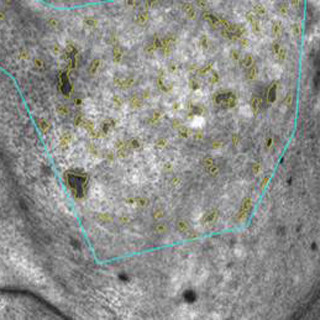

隠れジミは、肌の奥に潜むメラニンで、シミ予備軍とも呼ばれるもの。肌のターンオーバー(新陳代謝)により肌の表面に押し出され排出さるが、ターンオーバーが乱れると、肌の奥に留まってしまうことが知られていた。

これまでの研究から、トマトジュースの飲用により隠れジミが改善され、その効果がカロテンの一種であるβ-カロテンによるものである可能性が報告されていた。今回の研究は、トマトジュース以上にβ-カロテンを含有している野菜・果実ミックスジュースにも隠れジミの改善効果があるのかどうかをヒト試験にて確認したもので、継続して飲用した結果、隠れジミが減少することを確認したほか、この効果の有効成分が、β-カロテンやα-カロテンのようなカロテン類であることが示唆されたとしている。